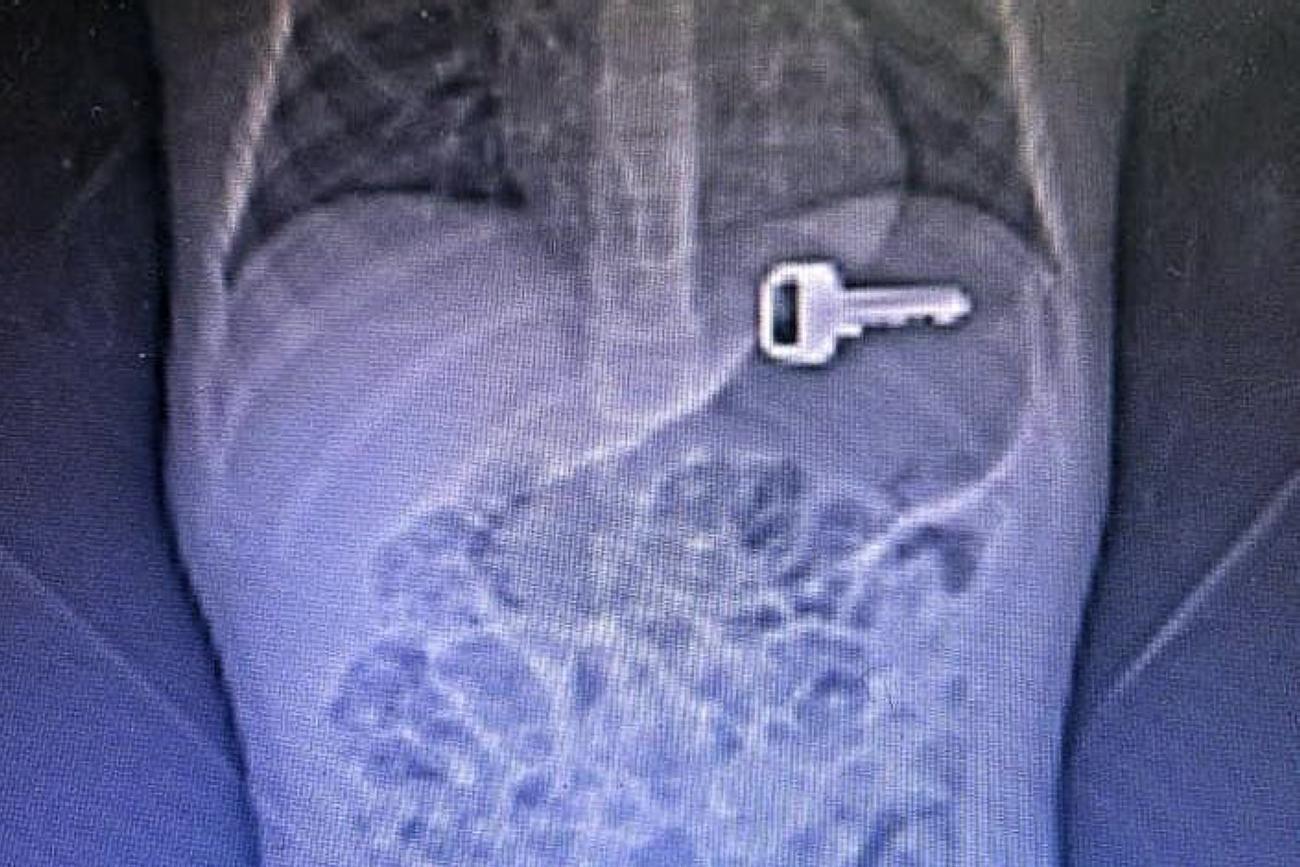

Salime destaca que os objetos mais comuns em casos de engasgamento são moedas, chaves, pregos, baterias de relógio e pilhas. Ela lembra que certos alimentos, como uvas, pipoca, balas duras e pedaços de carne, além de pequenos brinquedos, podem causar esse tipo de acidente. "Todos esses objetos extraídos das crianças colocamos em um cofre que usamos depois para orientações”, disse.

Assim que o paciente chega ao hospital, ele passa por uma série de exames de imagem para localizar e identificar o tipo do objeto ingerido. A extração acontece por dois métodos: o processo endoscópico, utilizado em casos mais simples, e a cirurgia, necessária em casos mais graves que podem evoluir a óbito, como a ingestão de baterias e pilhas, além itens perfurocortantes, como pregos ou agulhas.